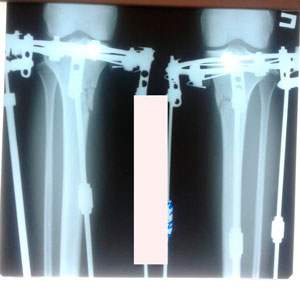

Дата операции - 07.11.2019г.

Дата снятия аппаратов - 15.02.2020

Срок сращения 92 дня.